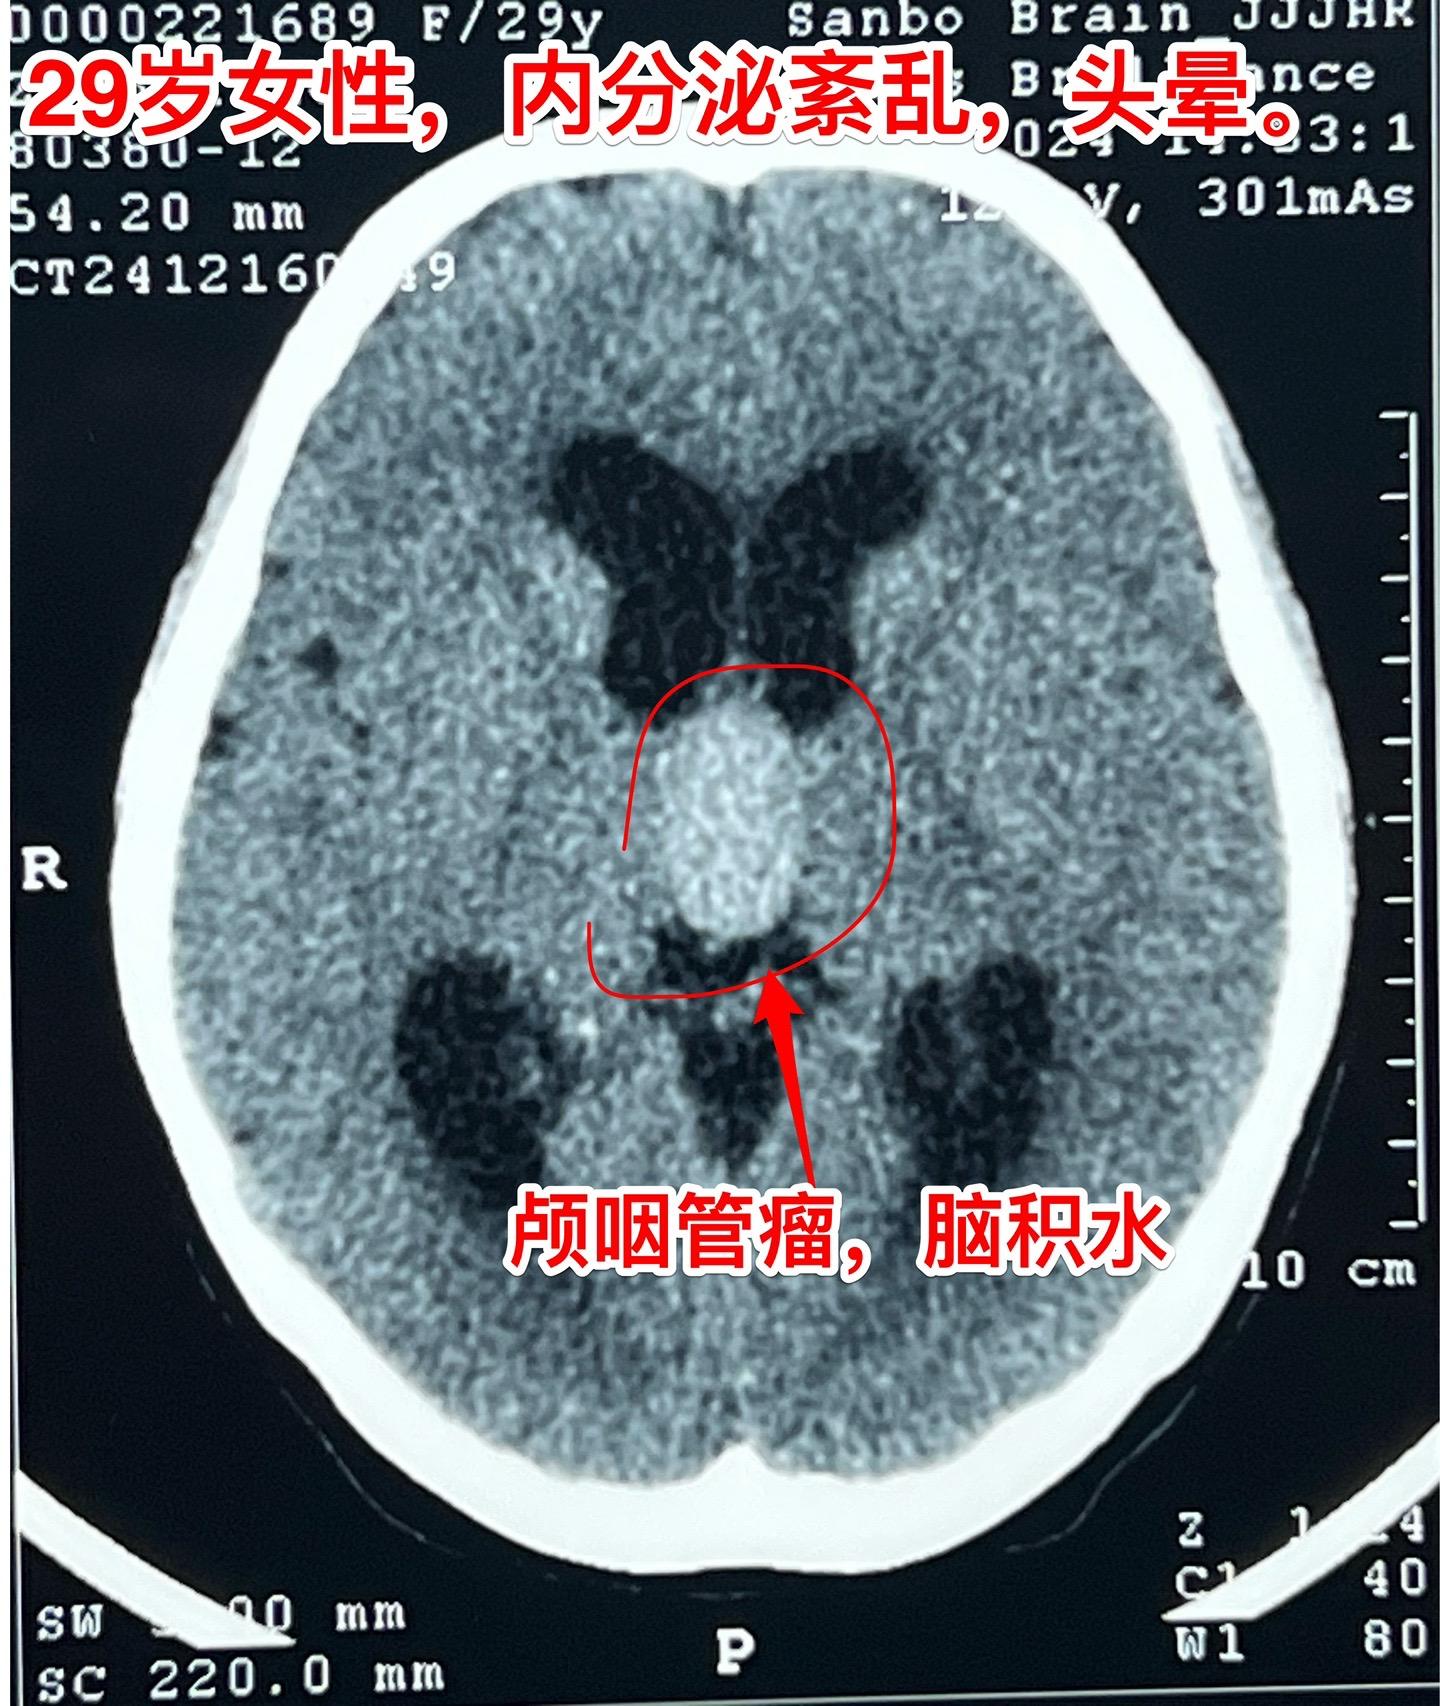

大理市女教师患颅咽管瘤。29岁大理市女老师,因头晕,内分泌功能障碍到医院行脑部CT及磁共振检查,发现颅咽管瘤。CT显示肿瘤有钙化,是典型的造釉细胞性颅咽管瘤。 患者家人系医务工作者。发现颅咽管瘤后即来北京就医。到我院检查视力视野,有视野缺损。 今日在我科作了颅咽管瘤切除手术,手术后5小时病人即清醒了。肿瘤完全切除,垂体柄结构完整,漏斗保留约三分之一。